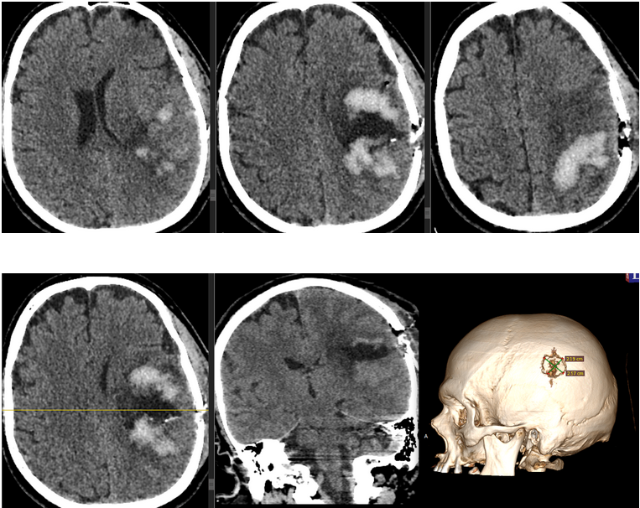

Инсульт удаление гематомы

Инсульт удаление гематомы 108 фотографий